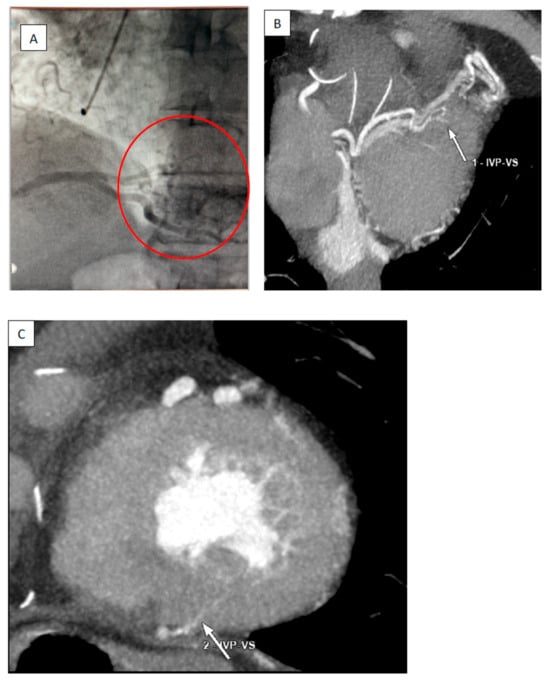

2. Case Report

Surgical Technique